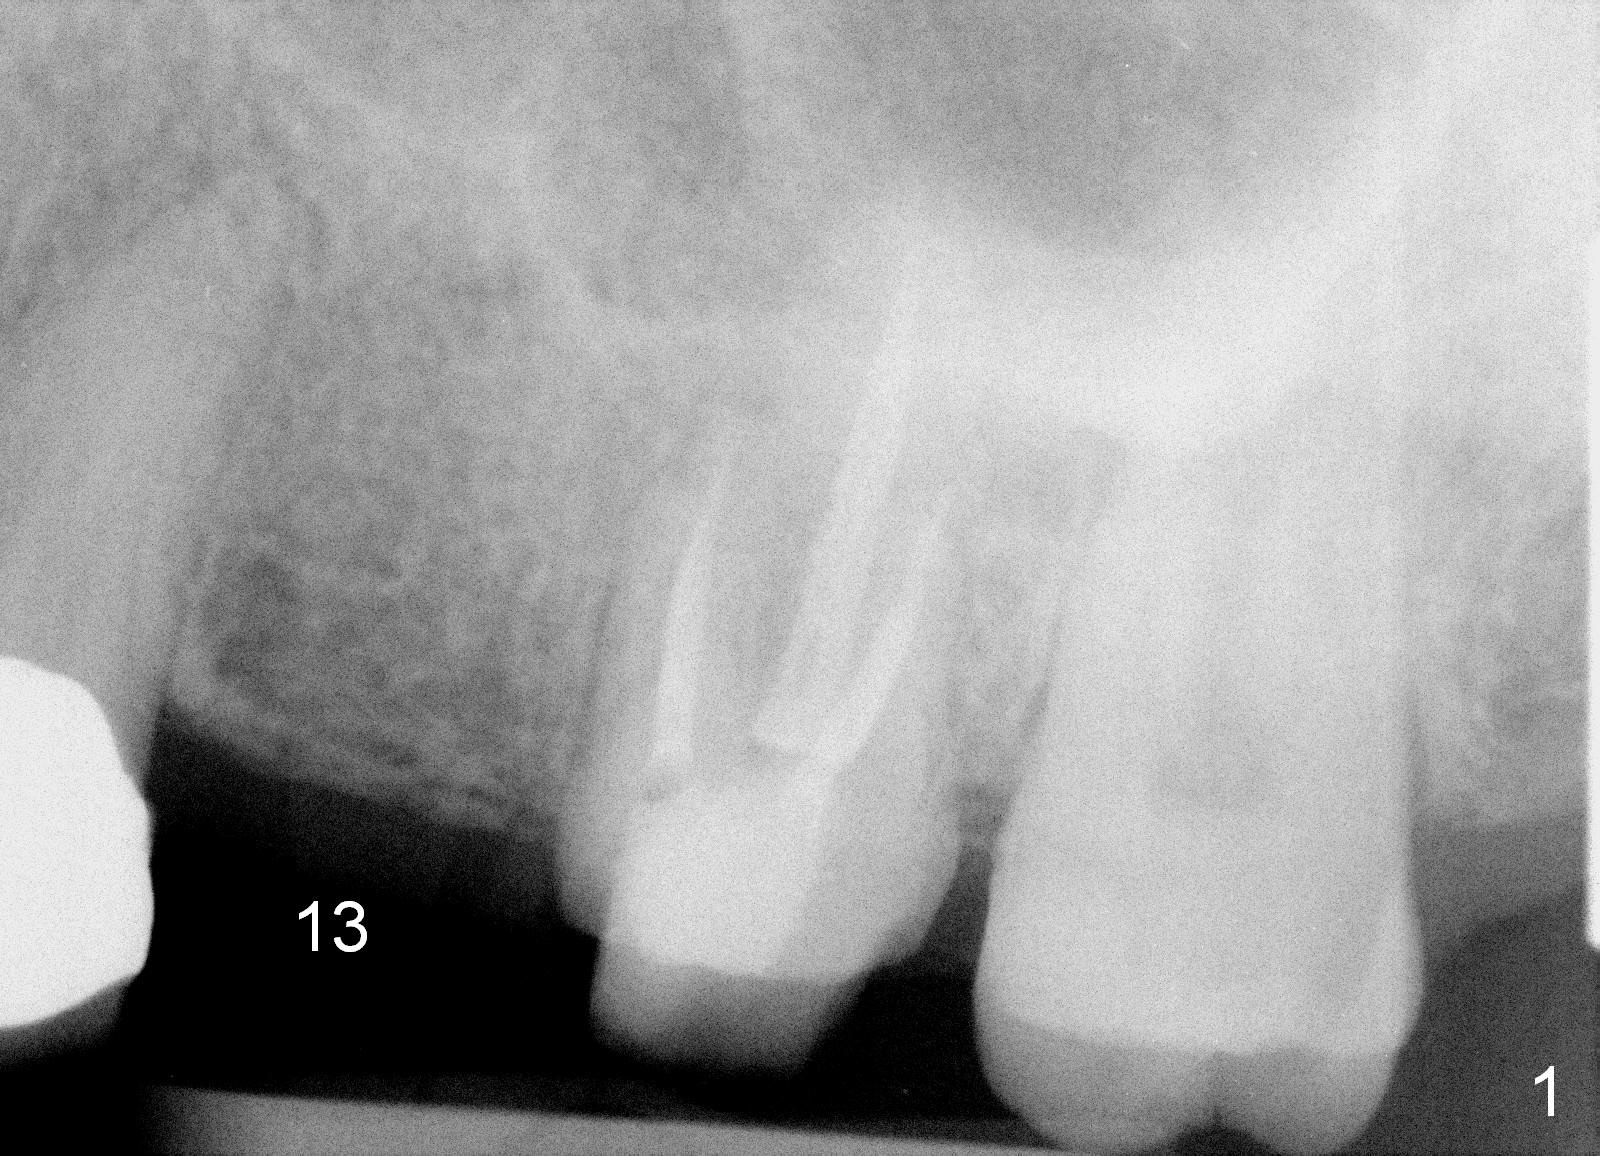

A 45-year-old lady is nervous about dental treatment. The missing tooth #13 was replaced by a 3-unit bridge. The latter is sectioned because the posterior abutment has caries. PA in Fig.1 is taken when root canal therapy and build up are finished. Fig.2 shows the wide edentulous area with a single-unit crown being tried in for #14. Osteotomy is initiated with the crown in place without cementation, since it is easy to determine the mesiodistal position (Fig.3 red lines). Without the crown in place, osteotomy tends to be distal. In this case, the osteotomy is later attempted to be moved distally with Lindamann bur and deepened to 14 mm from the gingival margin (Fig.4). A 2.5 mm reamer is being used at 50 RPM to increase osteotomy with difficulty. Drills have to used at high RPM instead (Fig.5 4x14 mm). A 4.5x14 mm tissue-level implant is placed with insertion torque >60 Ncm (Fig.6 I); a 4x3 mm abutment (A) is placed immediately for an immediate provisional. Fig.7 is taken 7 days postop to show the gingival recipient site formed by the provisional. The patient is so afraid of X-ray that the next one is taken 1.5 years post cementation (Fig.8). It appears that dense bone bundle forms between the crest and the 1st implant thread (adaptation functional change, arrowheads). The bone density continues to increase 2 years 8 months post cementation (Fig.9 *, 10); the bone has grown into the area between the 1st 2 threads (arrow).